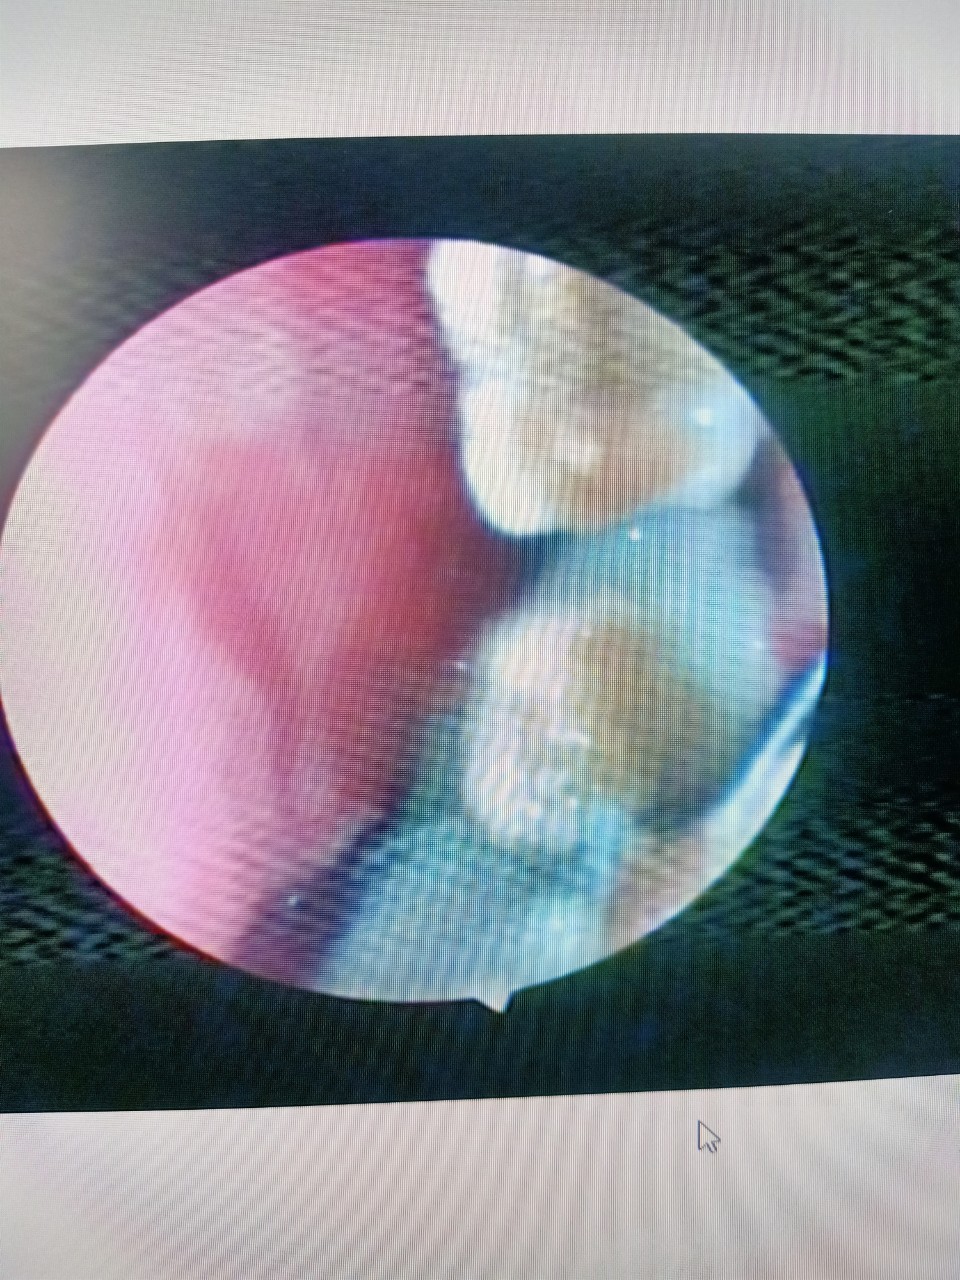

Qua nội soi, bác sĩ phát hiện trong hốc mũi trái của bệnh nhân có một khối rất cứng, sù sì. Bác sĩ chẩn đoán chị H bị sỏi rất hiếm gặp vùng mũi. Ngay sau đó, bác sĩ đã hút dịch xung quanh để kiểm tra và xử lý.